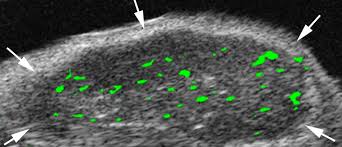

immagine ecografica con  mezzo di contrastoL'ecografia con mezzo di contrasto puo' essere di ausilio nella  diagnosi differenziale delle lesioni focali epatiche subcentimetriche dall'aspetto dubbio alla TC multistrato

To evaluate whether the use of contrast-enhanced ultrasound (CEUS) could improve the characterization of indeterminate subcentimetric focal liver lesions (FLLs) seen with multidetector computed tomography (MDCT) in cancer patients.

For 12 months all patients with extrahepatic tumors showing small (< 10 mm), indeterminate focal liver lesions on whole-body or abdominal computed tomography (CT) underwent immediate, targeted ultrasound (US) to rule out a cystic lesion. Whenever unenhanced US demonstrated a non-cystic lesion or failed to recognize any focal abnormality within the suspected area, CEUS was carried out. During the arterial phase, CEUS was focused on the area reflecting the CT finding, while the entire organ was explored during the portal-sinusoidal phase.

Among the 132 patients with MDCT evidence of indeterminate, subcentimetric focal liver lesions (206 lesions), US proved the cystic nature of 138 lesions in 87 patients. In 45 cases US failed to recognize any abnormality or cystic image and these subjects underwent CEUS. The CEUS results were confirmed by further assessment or follow-up for 43 / 45 patients (3 cysts, 8 hemangiomas, 47 metastases, 2 areas of focal steatosis, 2 eosinophilic necroses, 1 granuloma, 1 abscess, 1 fistula). CEUS failed to detect 3 lesions (1 metastasis and 2 benign lesions). In 8 cases CEUS recognized additional liver metastases.

CEUS can be helpful in demonstrating or excluding metastases in cancer patients with MDCT evidence of subcentimetric, indeterminate focal liver lesions.